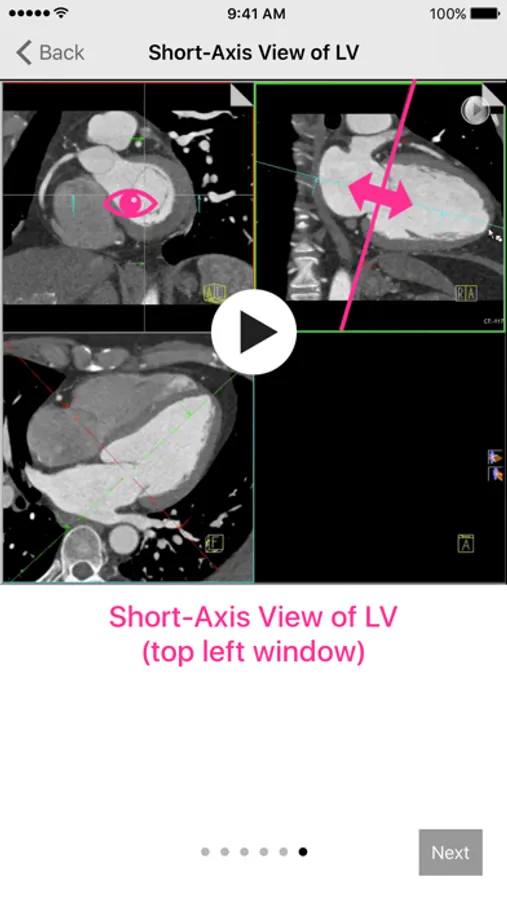

• Short-Axis View of the Left Ventricle